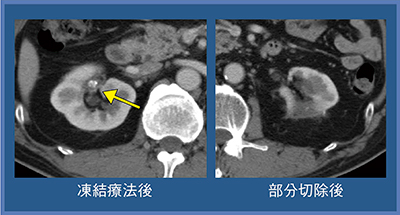

症例3(80歳代,男性)は,腫瘍径3.8cmのclear cell RCCで,糖尿病,慢性腎不全,陳旧性心筋梗塞があり,抗凝固薬3剤服用の手術ハイリスク症例のため凍結療法を施行した。ニードル4本にて治療を行ったが,傷の治りが悪く膿瘍が生じたため,ドレナージと抗菌薬で治療を行っている(図6)。

図6 症例3:合併症 膿瘍(80歳代,男性)